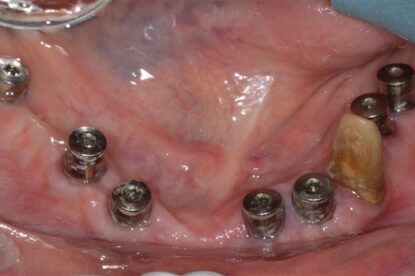

Ακόμη ένα περιστατικό ολικής στοματικής αποκατάστασης ασθενούς με ακίνητες γέφυρες στηριζόμενες σε εμφυτεύματα(8 στην άνω και 7 στην κάτω γνάθο).